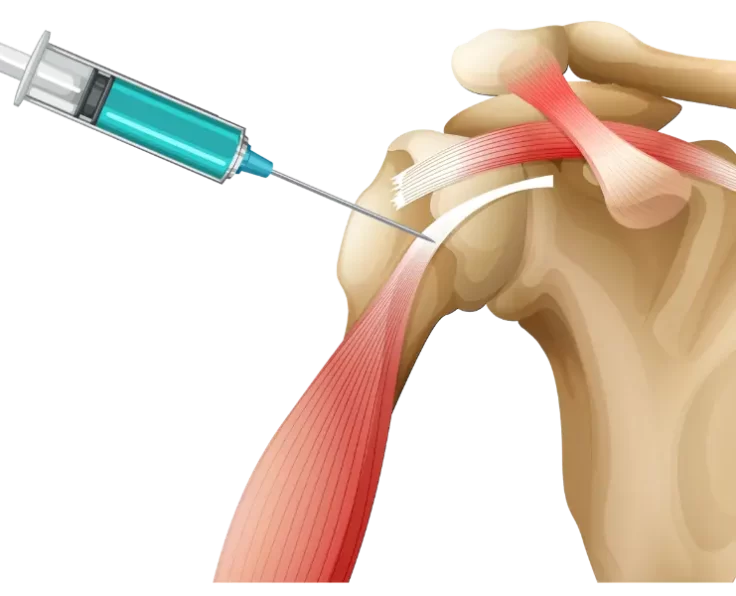

PRP for Shoulder

Platelet Rich Plasma therapy, or PRP, is a non-healing muscle and tendon injury treatment option for people with SCI who have shoulder pain (Spinal Cord…